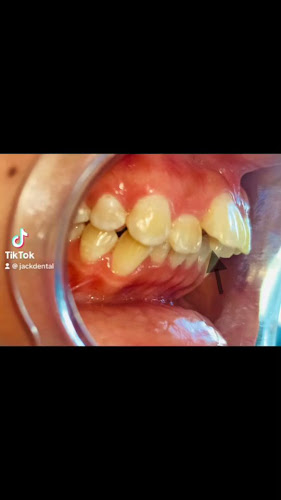

Información sobre JACKDENTAL, Dentista en La Libertad (Santa Elena)

Aquí podrás encontrar ubicación, horarios, horas más concurridas, contacto, fotos y opiniones reales hechas por usuarios.